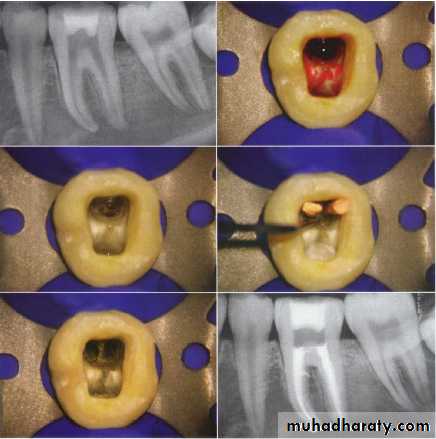

(lateral condensation)

Procedure of master cone selection(the cone that occupies most of the root canal parts):-the master cone selected should have the same size of the M.A.F(master apical file) and it should have the same length of the full working length.

The master cone should need some force to be seated inside the canal and some force is required to dislodge the master cone from the canal. This is called tug-back. This resistance of removal of the master cone enhances the sealing ability at the apical area of the root canal.

Gutta percha

If the master cone goes to the full working length but its loose inside the canal , we take larger gutta-percha cone or we remove 1mm from the apical end of the master cone to increase the width of the master cone.

Verify the master cone position with a radiograph to ensure the optimum fitness.

Mix the sealer and coat the wall by picking up sealer on M.A.F and spin it counter-clockwise . once the M.A.F is rotated , there will painting of the walls with the sealer.

Dip the tip of master cone in the sealer and seat it in the root canal.

• By the use of the spreader the master cone is pushed laterally and apically providing room for auxiliary gutta-percha point . the spreader should rotate 180o (to the right and left) until it becomes loose and pushed out side.

• The spreader should penetrate the apical 1\3 (a rubber stopper should be placed to mark the length of penetration 2-3mm. from the tip of the master cone)

• Place an auxiliary cone (which is smaller than the master cone )after its tip is dipped in the sealer.

repeat the process by more gutta-percha points and more spreading until the entire canal is filled when the spreader cant be placed beyond the cervical line of the root canal.

take aradiograph to check the obturation mass.

a hot instrument is used to cut the excess gutta-percha to just below the cervical line. The instrument used can be either an excavator or ash no.6 and should be very hot to cut in one motion. If the instrument is not hot enough then the master cone might be dislodged.

aplugger is used for vertical condensation to assure tightness of the condensation.

all the sealer and gutta-percha should be removed from the pulp chamber by a round bur.

the cement base material and a coronal restoration are placed in the tooth..